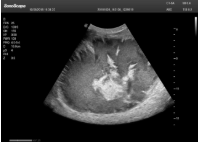

1單晶體凸陣探頭

采用了單晶體探頭材料,探頭面是凸面,接觸面小,成像視野呈扇形,應(yīng)用廣泛,常應(yīng)用于腹部、婦產(chǎn)、肺部等相對部位較深的臟器。

超聲圖像是探頭和系統(tǒng)平臺緊密結(jié)合的產(chǎn)物,因此在同一臺機(jī)器上,軟件、硬件都需要達(dá)到單晶探頭的要求。